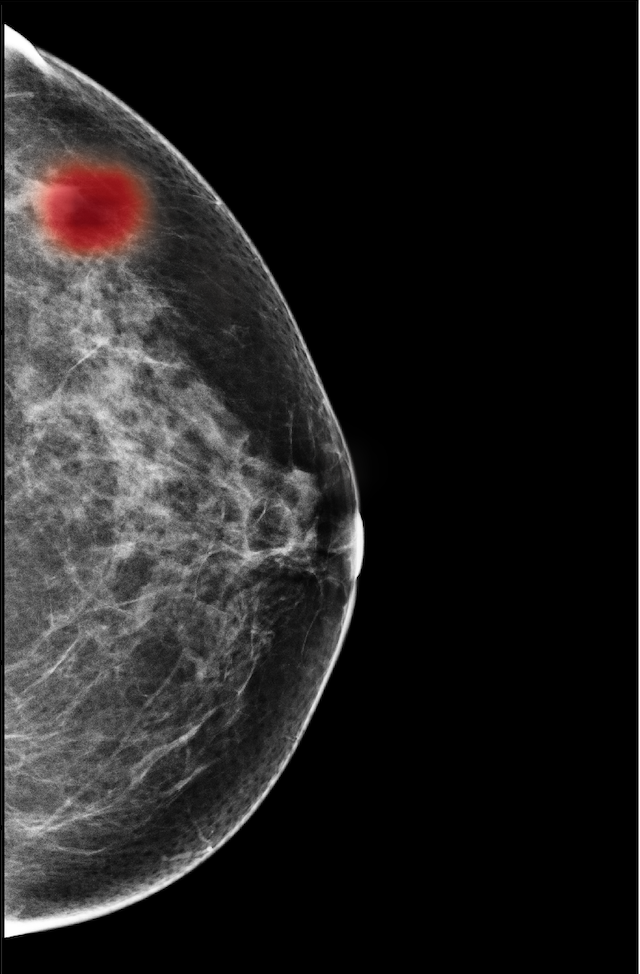

In Figure 7, we visualize saliency maps for four samples selected from the test set. In the first two examples, the saliency maps are highly activated on the annotated lesions, suggesting that our model is able to detect suspicious lesions without pixel-level supervision. Moreover, the attention is highly concentrated on ROI patches that overlap with the annotated lesions. In the third example, the saliency map for benign findings identifies three abnormalities. Although only the top abnormality was escalated for biopsy and hence annotated by radiologists, the radiologist’s report confirms that the two non-biopsied findings have a high probability of benignity and a low probability of malignancy. In the fourth example, we illustrate a case when there is some level of disagreement between our model and the annotation in the dataset. The malignancy saliency map only highlights part of a large malignant lesion with segmental coarse heterogeneous calcifications. This behavior is related to the design of : a fixed pooling threshold cannot be optimal for all sizes of ROI. The impact of is further studied in 3.6. This example also illustrates that while human experts are asked to annotate the entire lesion, CNNs tend to emphasize only the most informative regions. While no benign lesion is present, the benign saliency map still highlights regions similar to that in the malignancy saliency map, but with a lower probability than the malignancy saliency map. In fact, calcifications with this morphology and distribution can also result from benign pathophysiology [42].

The NYU Breast Cancer Screening Dataset [78] includes 229,426 exams (1,001,093 images) from 141,472 patients.222Our retrospective study was approved by our institutional review board and was compliant with the Health Insurance Portability and Accountability Act. Informed consent was waived. Each exam contains at least four images which correspond to the four standard views used in screening mammography: R-CC (right craniocaudal), L-CC (left craniocaudal), R-MLO (right mediolateral oblique) and L-MLO (left mediolateral oblique). An example is shown in Figure 3.

For all exams matched with biopsies, we asked a group of radiologists (provided with the corresponding pathology reports) to retrospectively indicate the location of the biopsied lesions. This way we obtained the segmentation labels: where if pixel belongs to the benign/malignant findings. An example of such a segmentation is shown in Figure 3. In all experiments (except for experiments in Section 3.6 that assess the benefits of utilizing segmentation labels), segmentation labels are only used for evaluation. We found that, according to the radiologists, approximately of exams were mammographically occult, i.e., the lesions that were biopsied were not visible on mammography, even retrospectively, and were identified using other imaging modalities: ultrasound or MRI.